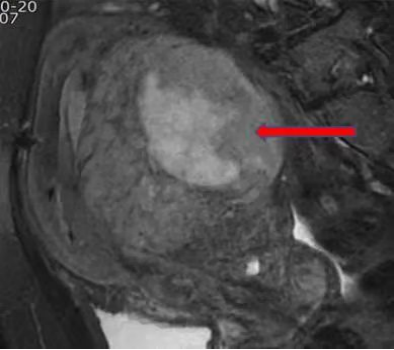

确实,过去我们检查子宫肌瘤,都选择价格便宜且快捷的超声。在确诊子宫肌瘤这方面占据了不可或缺的地位,对于一般没有症状的子宫肌瘤患者,超声检查仍然是首选的手段。 但是,对于有症状的子宫肌瘤患者,以及需要评估子宫肌瘤是否影响生育的患者,更推荐做磁共振检查。 磁共振检查可以获取整个盆腔的信息,可以从不同角度了解子宫及子宫肌瘤的情况。从而清楚的知道每个子宫肌瘤在什么位置上,是哪个肌瘤引起的临床症状,这个肌瘤如果继续长大,会不会对生育有影响等等问题。 磁共振检查能够辅助判断一个病灶是良性的还是恶性子宫肌瘤。 对于现在采用的一些微创手术如腹腔镜,在术前进行磁共振评估,能更好设计子宫上切口,从而最合适的切口进行子宫肌瘤的剔除。 左图蓝色箭头所示粘膜下肌瘤,右图红色箭头所示浆膜下肌瘤,黄色箭头所示肌壁间肌瘤,都能在磁共振上清楚的显示出来。 此图红色箭头所示为子宫肉瘤,磁共振清晰可见病灶范围,大小。 因此,对于子宫肌瘤治疗方式的选择,怀孕前评估子宫肌瘤对生育的影响,术前进行磁共振检查都是值得的。 九江市第一人民医院开发区分院/柯炜